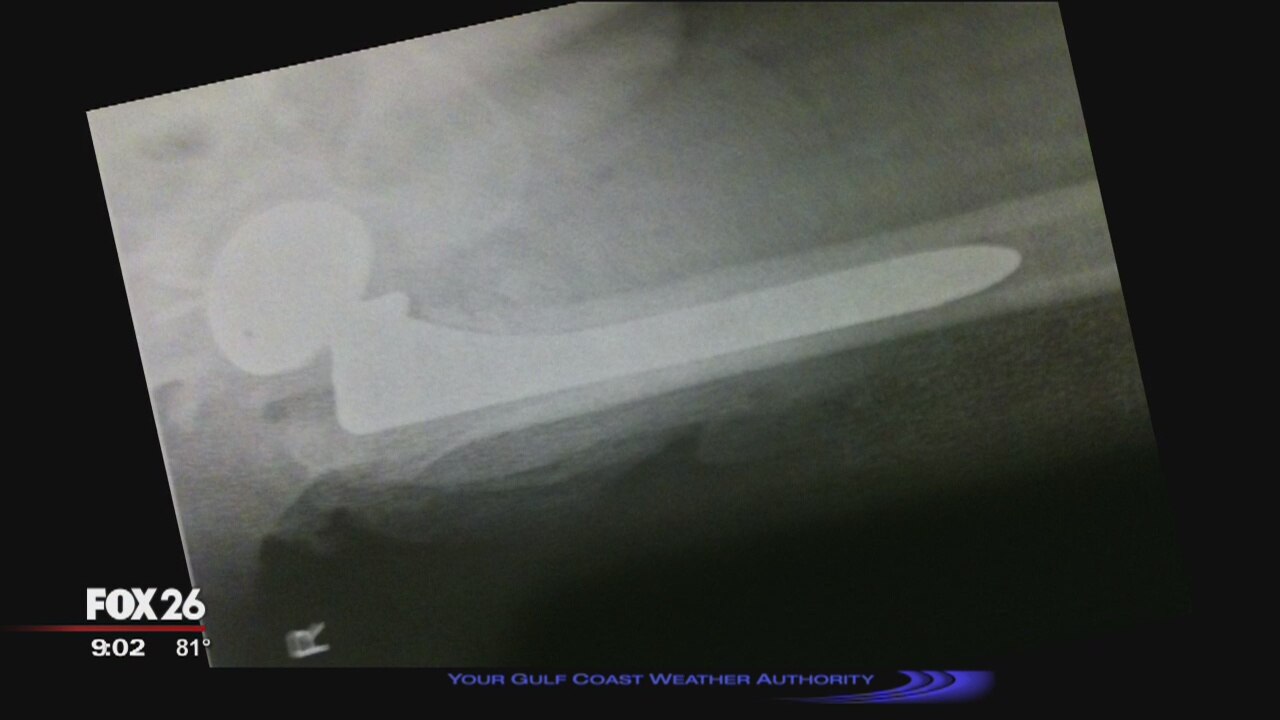

Hundreds of lawsuits filed against manufacturer of medical device